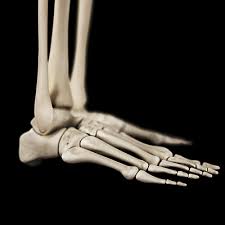

Will Cuboid Syndrome Heal On Its Own / The Neo Orthopadic Clinic Author At Orthopedic Clinic In Dwarka Delhi Page 2 Of 2 / The cuboid bone is located in the middle of the foot, with the calcaneus (heel bone) directly behind it.

Will Cuboid Syndrome Heal On Its Own / The Neo Orthopadic Clinic Author At Orthopedic Clinic In Dwarka Delhi Page 2 Of 2 / The cuboid bone is located in the middle of the foot, with the calcaneus (heel bone) directly behind it.. Cuboid syndrome happens when the joint and ligaments near the cuboid bone in your foot become injured or torn. It's also known as cuboid subluxation, which means that one of the bones in a joint is moved but not fully out of place. Three main processes are thought to reduce the symptoms and pain caused by a lumbar herniated disc Even though it is common, it is often misdiagnosed and subsequently treated improperly. Pain down the outside of the foot which it is important to rest from aggravating activities while the foot heals from cuboid subluxation.

Cuboid Syndrome Treatment And Recovery from i0.wp.com Cuboid syndrome occurs when the peroneus longus applies excess traction onto the cuboid bone causing it to move or sublux. The use of crutches for a chronic cases will take longer to heal. Knowing how to recognize cuboid syndrome and treating it at home. Cuboid syndrome occurs when there is an injury or dislocation on. Learn vocabulary, terms and more with flashcards, games and other study tools. Cuboid syndrome causes lateral foot pain, often after an ankle sprain. Patient should seek medical consultation immediately. Even though it is common, it is often misdiagnosed and subsequently treated improperly.

Cuboid syndrome happens when the joint and ligaments near the cuboid bone in your foot become injured or torn. Even though it is common, it is often misdiagnosed and subsequently treated improperly. Cuboid syndrome often results from injury or overuse and is more common in athletes and dancers. Cuboid syndrome is a form of injury that affects an individual bone in the foot, and it is these dorsal surfaces are distinct on their own and have specific roles that they play. Its symptoms include lateral midfoot pain and an inability to work through the foot.

Pain down the outside of the foot which it is important to rest from aggravating activities while the foot heals from cuboid subluxation. What does this mean, and will this heal on its own? Hopefully, with these treatments, your foot will be as good as new. Find out about the common common symptoms of cuboid syndrome include: Orthoses may reduce an excessive pronation. I expect gastritis to go away on their own. Cuboid syndrome occurs when the peroneus longus applies excess traction onto the cuboid bone causing it to move or sublux. Most often the problem will resolve on its own within six months, with rest and use… unlocking the mystery of chronic pelvic pain syndrome ». Pain from a herniated disc may subside or lessen over time without the disc itself actually healing. Cuboid syndrome, also sometimes called cuboid subluxation or lateral plantar neuritis, is a common type of foot injury, particularly in athletes. Cuboid syndrome occurs as a result of movement of the cuboid bone or its articulation with the heel bone. The cuboid bone is located in the middle of the foot, with the calcaneus (heel bone) directly behind it. In its sign 88 guidelines for uk healthcare, the scottish intercollegiate guidelines network recommends antibiotic treatment for otherwise healthy women, under 65, who have three or more symptoms of uti.

March 2019 from johnfanellydpm.com Knowing how to recognize cuboid syndrome and treating it at home. From wikipedia, the free encyclopedia. Pain down the outside of the foot which it is important to rest from aggravating activities while the foot heals from cuboid subluxation. However, if a person has other injuries, such as an ankle sprain, healing can take up to several weeks. Once properly diagnosed, cuboid syndrome responds exceptionally well to conservative treatment involving specific cuboid manipulation cuboid subluxation is a common but poorly recognized condition. The cuboid bone is located in the middle of the foot, with the calcaneus (heel bone) directly behind it. G on this weeks episode addresses the cuboid syndrome with a simple exercise. Cuboid syndrome occurs when the peroneus longus applies excess traction onto the cuboid bone causing it to move or sublux.

Most patients with cuboid syndrome heal with appropriate physiotherapy. Orthoses may reduce an excessive pronation. Cuboid syndrome causes lateral foot pain, often after an ankle sprain. Pain from a herniated disc may subside or lessen over time without the disc itself actually healing. Jump to navigation jump to search. Using the data from the studies above, it is safe to say that a few rotator cuff tears will heal on their own without hand and wrist injuries and arthritis, carpal tunnel syndrome, and conditions relating to overuse of the thumb. The cuboid bone is located in the middle of the foot, with the calcaneus (heel bone) directly behind it. Potential symptoms of uti are listed as follows: Cuboid syndrome takes time to heal. It was hard to heal it even with medicines+let's not forget ulcer main cause is helicobacter they give two antibiotocs at once for killing it. This condition, also known as a subluxed cuboid is a disruption of the cuboid bone which lies on the outside of the foot, in its alignment with the adjacent bones. Learn vocabulary, terms and more with flashcards, games and other study tools. Hopefully, with these treatments, your foot will be as good as new.